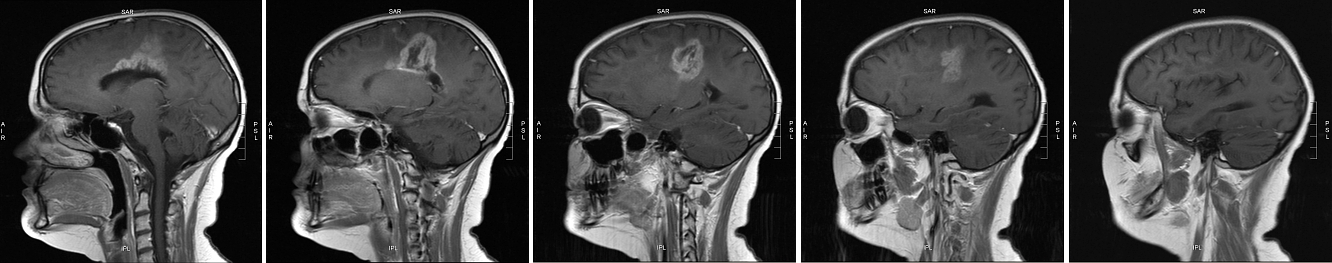

The images below are another view on the growth you see above. The top series is from 10 April 2007; the bottom from 21 May. Each series starts at the midline in the brain (the dividing line between left and right hemispheres) and proceeds out toward Meghan’s left ear. Note that the April scans begin slightly closer to the midline (you can see Meghan’s spinal cord in the first image). This means each April image comes “before” (closer to the midline than) its corresponding May image.

side view May 2007 series side view June 2007 series